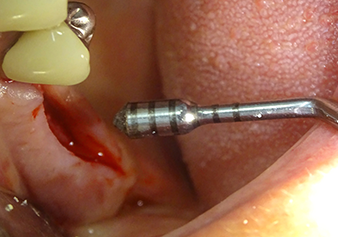

Dopo la preparazione atraumatica del lembo mucoperiosteo, con l'ausilio dello strumento I1 è stata contrassegnata la posizione e preparata la sede dell'impianto fino ad avvertire la resistenza iniziale. Gli strumenti piezochirurgici sono stati utilizzati eseguendo un movimento verticale ascendente e discendente senza dover esercitare alcuna pressione. La vibrazione piezoelettrica ha generato la cavitazione richiesta ad elevata efficienza.

Lo strumento I2A (diametro 2,0 mm) è stato quindi impiegato per perforare il pavimento sinusale in modo graduale e su superfici molto ridotte. Tale metodo piezochirurgico previene il danneggiamento della membrana di Schneider. Durante l'utilizzo di Z25P, la membrana risultava già essere leggermente sollevata dal fluido di raffreddamento fornito attraverso la punta dello strumento (Fig. 3). La quantità di fluido di raffreddamento presente era solo del 50% per evitare che la sede dell'impianto registrasse un'elevata pressione.